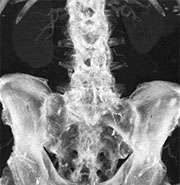

The dual energy imaging with facilitated bone and plaque removal significantly improves diagnostic confidence of CT angiographic imaging of the entire vascular territory. This technique is particularly helpful in patients with advanced atherosclerosis, when conventional CT angiograms are difficult to interpret.

In this context, the dual energy technique has markedly simplified bone removal on cerebrovascular, abdominal and peripheral run-off studies, replacing a laborious and time-consuming manual chore by an easy step that takes less than a minute to perform on a workstation for image analysis and post-processing.

In addition, based on a newly developed software algorithms, the dual energy technique allows the automated removal of calcified plaque from the vessel. This permits to readily detect and display narrowed segments of the arterial tree otherwise obscured by overlying calcifications without time-consuming manual post-processing. This technique is particularly helpful in patients with advanced atherosclerosis, when conventional CT angiograms are difficult to interpret.

Overall, dual energy imaging with facilitated bone and plaque removal overcomes limitations of standard CT, improves diagnostic confidence of CT angiographic imaging of the entire vascular territory and is expected to improve patient care.